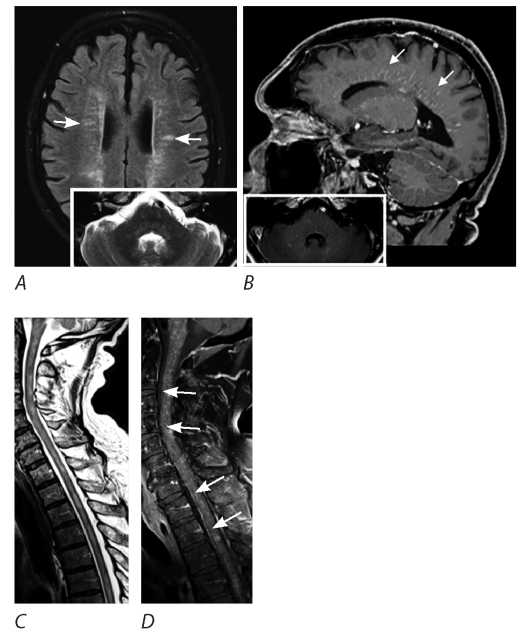

- МРТ головного мозга (ноябрь 2022 г.): в сравнении с исследованием от апреля 2021 г. — отрицательная динамика в виде увеличения диффузных Т2-гиперинтенсивных зон в глубоком белом веществе обоих полушарий большого мозга, стволе мозга и обоих полушарий мозжечка, имеющих протяжённый и периваскулярный паттерн, интенсивно накапливающих КВ (рис. 3);

Рис. 3. МРТ головного мозга пациента М. (ноябрь 2022 г.).

Т1+С: накопление КВ в перивентрикулярном и глубоком белом веществе полушарий головного мозга (А–С), в стволе (С, D), ножках мозга (D), в обоих полушариях мозжечка (А, D).

Fig. 3. Patient M.'s brain MRI (November 2022).

Т1+С: contrast enhancement in the periventricular and deep white matter of the cerebral hemispheres (А–С), the brainstem (С, D), the cerebral peduncles (D), and both cerebellar hemispheres (А, D).